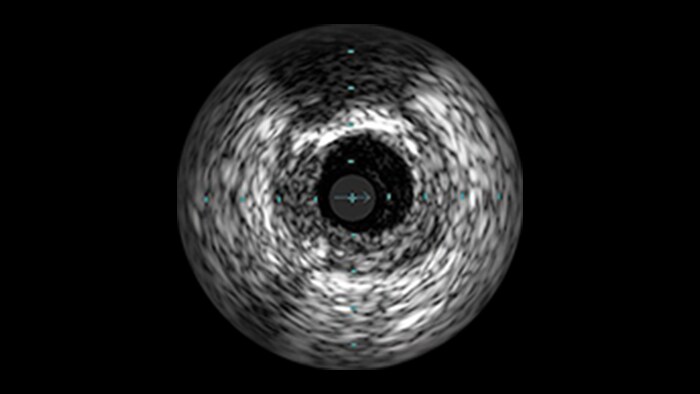

Diffuse Disease

Approximately 20% of the coronary lesions treated today are long and diffuse.1,2

Clinical challenges

– Stent length is an independent predictor of in-stent restenosis and thrombosis.

– Stenting long segments with multiple and or overlapping stents may lead to injury to the vessel wall integrity.

– Diffuse CAD may be underestimated by evaluation with coronary angiography.

– Determining reference vessel sizing can be challenging when the vessel is diffusely diseased.

IVUS-guided vs. angiography-guided outcomes3

Advanced tools for optimal PCI outcomes